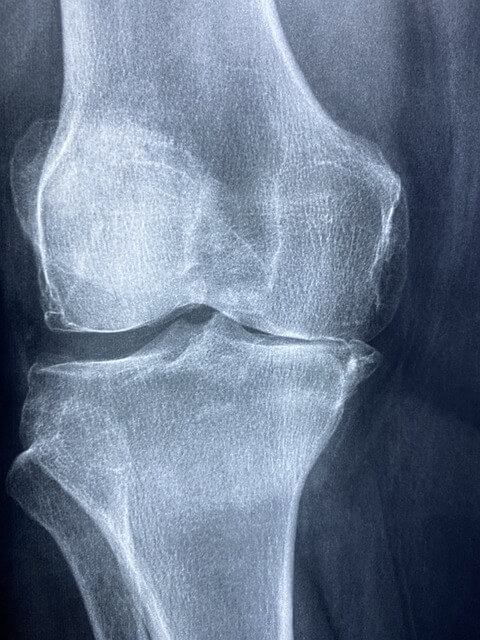

How do vets check for arthritis in dogs?

Arthritis in dogs is most commonly checked through x rays, which provide valuable insights into their condition.

However, there are other alternatives like blood tests and ultrasound too. With these options, you can get a full picture of your dog’s well-being and make informed decisions for their care.